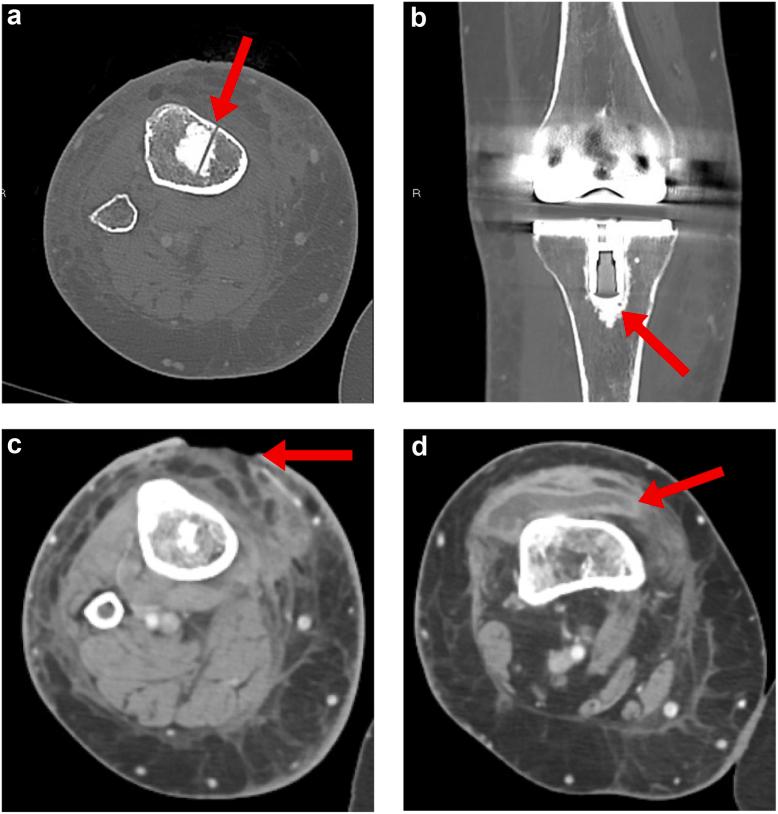

A 51-year-old woman suffered cardiac arrest requiring emergent intraosseous access that abutted the tibial component of her total knee arthroplasty. She developed a wound at the site and knee pain which was concerning for deep infection. Subsequent imaging was consistent with osteonecrosis developing around the tibial component. The component eventually loosened, requiring a revision surgery. Her deep cultures remained negative throughout. Her findings are most consistent with osteonecrosis and aseptic loosening of her prosthesis. While intraosseous access may be beneficial during resuscitation, it has complications. This is the first reported case of osteonecrosis secondary to intraosseous access leading to prosthetic loosening necessitating a revision surgery.

一名51岁女性发生心脏骤停,需要紧急进行骨内通路穿刺,穿刺部位紧邻其全膝关节置换术的胫骨部件。她在该部位出现了伤口和膝关节疼痛,令人担心发生深部感染。后续影像学检查结果与胫骨部件周围发生的骨坏死相符。该部件最终松动,需要进行翻修手术。她的深部培养物始终呈阴性。她的检查结果最符合假体的骨坏死和无菌性松动。虽然骨内通路在复苏过程中可能有益,但也存在并发症。这是首例报告的因骨内通路继发骨坏死导致假体松动并需要翻修手术的病例。